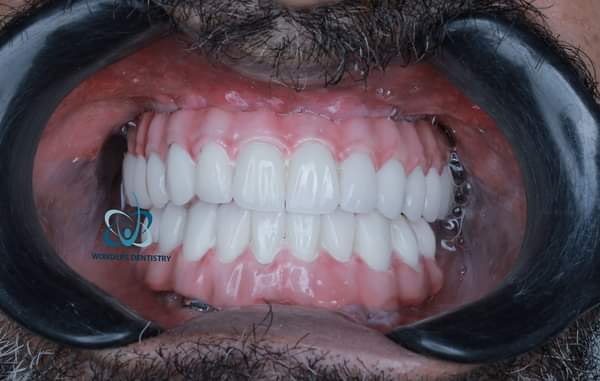

النتيجة النهائية

مع الغرسات الوجنية، اصبح لدى المريض ابتسامة جميلة و طبيعية المظهر، مما حسن بشكل كبير قدرته على العض و المضغ و التحدث بثقة مرة اخرى.

في الزيارة الأخيرة، يتم ربط الأطراف الصناعية الدائمة المصممة بالغرسات الوجنية. يتأكد طبيب الأسنان من أن عضتك صحيحة و أن أسنانك الجديدة تعمل بسلاسة